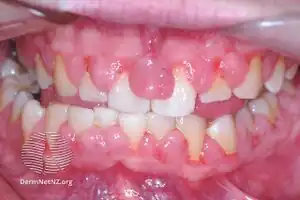

| Gingivitis, a common cause of inflammatory gingival enlargement. | |

Gingival enlargement has a multitude of causes. The most common is chronic inflammatory gingival enlargement, when the gingivae are soft and discolored. This is caused by tissue edema and infective cellular infiltration caused by prolonged exposure to bacterial plaque, and is treated with conventional periodontal treatment, such as scaling and root planing.[1]